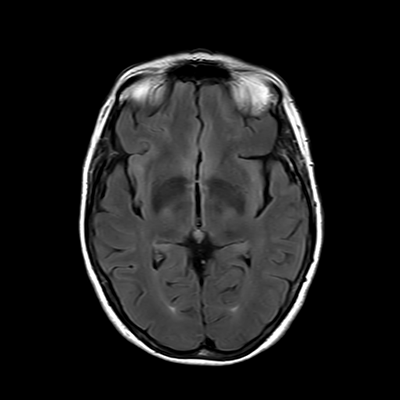

You also obtain an MRI of his brain once it's clinically safe to do so.

MRI brain (FLAIR)

You are now very concerned that he truly has an infectious meningoencephalitis.